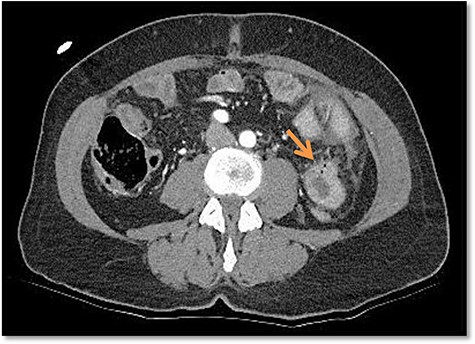

Due to the unclear sonography findings, a computed tomography (CT) scan was performed, which was concerning for a bowel perforation and traumatic hematoma of the jejunum in the left upper quadrant (Fig. 2). Also rib fractures of left costae VII, IX–XII were detected.